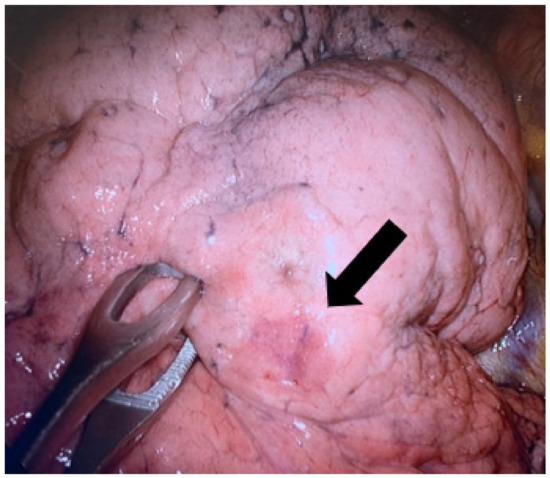

2.3. Surgical Approach

After the radiological procedure, a patient was returned ito the ward and surgery was scheduled for the same day of plug deployment, though at least 3 h later (the time required for the plug’s expansion). We performed a uniVATS procedure under general anesthesia according to Gonzales Rivas’ approach [28]. After the lung collapse, visceral pleura were carefully inspected until direct visualization of the hydrogel plug was confirmed. Once the marked lesion was identified, a large-ring forceps was used to remove the lesion with the surrounding lung parenchyma with a margin distance of 2 cm and a wedge resection was performed (Figure 3). All lung specimens underwent frozen section examination in order to assess the lesions’ excision and its nature (benignant vs malignant). If a malignant cancer was confirmed, we proceeded to a major lung resection, and the type of resection (segmentectomy or lobectomy) depended mainly on the site of the lesion, as well as the percentage of solid component of the lesion (segmentectomy if it was less than 50% of the GGO). The study’s end points were the rate of intraoperative localization of marked lesions and the rate of successful uniVATS resections.

Figure 3. (A) Hydrogel plug sealed into lung parenchyma (uniVATS vision). (B) Lung specimen with hydrogel plug previously deployed (1 month before surgery).